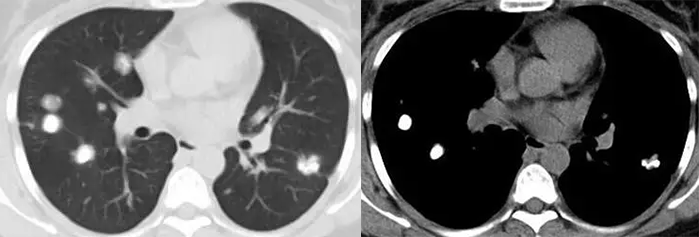

图片

女性,52 岁。胰腺癌双肺多发转移,大部分转移结节周围可见磨玻璃密度晕征。

男,50 岁。肾透明细胞癌伴肉瘤样癌。双肺空洞型肺转移,部分周围可见「晕征」。双肺另有不伴有空洞的转移结节。